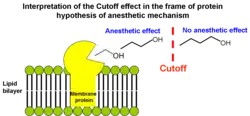

4. Effect vanishes beyond a certain chain length

According to the Meyer-Overton correlation, in a homologous series of any general anaesthetic (e.g. n-alcohols, or alkanes), increasing the chain length increases the lipid solubility, and thereby should produce a corresponding increase in anaesthetic potency. However, beyond a certain chain length the anaesthetic effect disappears. For the n-alcohols, this cutoff occurs at a carbon chain length of about 13[71] and for the n-alkanes at a chain length of between 6 and 10, depending on the species.[72]

If general anaesthetics disrupt ion channels by partitioning into and perturbing the lipid bilayer, then one would expect that their solubility in lipid bilayers would also display the cutoff effect. However, partitioning of alcohols into lipid bilayers does not display a cutoff for long-chain alcohols from n-decanol to n-pentadecanol. A plot of chain length vs. the logarithm of the lipid bilayer/buffer partition coefficient K is linear, with the addition of each methylene group causing a change in the Gibbs free energy of -3.63 kJ/mol.

The cutoff effect was first interpreted as evidence that anaesthetics exert their effect not by acting globally on membrane lipids but rather by binding directly to hydrophobic pockets of well-defined volumes in proteins. As the alkyl chain grows, the anaesthetic fills more of the hydrophobic pocket and binds with greater affinity. When the molecule is too large to be entirely accommodated by the hydrophobic pocket, the binding affinity no longer increases with increasing chain length. Thus the volume of the n-alkanol chain at the cutoff length provides an estimate of the binding site volume. This objection provided the basis for protein hypothesis of anaesthetic effect (see below).

However, cutoff effect can still be explained in the frame of lipid hypothesis.[31][73] In short-chain alkanols (A) segments of the chain are rather rigid (in terms of conformational enthropy) and very close to hydroxyl group tethered to aqueous interfacial region ("buoy"). Consequently, these segments efficiently redistribute lateral stresses from the bilayer interior toward the interface. In long-chain alkanols (B) hydrocarbon chain segments are located further from hydroxyl group and are more flexible than in short-chain alkanols. Efficiency of pressure redistribution decreases as the length of hydrocarbon chain increases until anaesthetic potency is lost at some point. It was proposed that polyalkanols (C) will have anaesthetic effect similar to short-chain 1-alkanols if the chain length between two neighbouring hydroxyl groups is smaller than the cutoff.[74] This idea was supported by the experimental evidence because polyhydroxyalkanes 1,6,11,16-hexadecanetetraol and 2,7,12,17-octadecanetetraol exhibited significant anaesthetic potency as was originally proposed.[73]